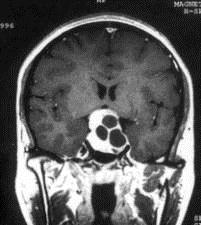

病历摘要:??患者男性,35岁。性功能减退2年,视力下降6月。既往体健。体检:神清,皮肤细腻,毛发稀疏。视力左眼0.3,右眼0.5,双瞳等大等圆,直径3....

问题 病历摘要:??患者男性,35岁。性功能减退2年,视力下降6月。既往体健。体检:神清,皮肤细腻,毛发稀疏。视力左眼0.3,右眼0.5,双瞳等大等圆,直径3.5mm,对光反射稍迟钝,双颞侧偏盲,双眼底视神经乳头原发性萎缩,余神经系统未见异常。 术前的准备应包括下列哪些?提示:拟经蝶窦入路手术治疗